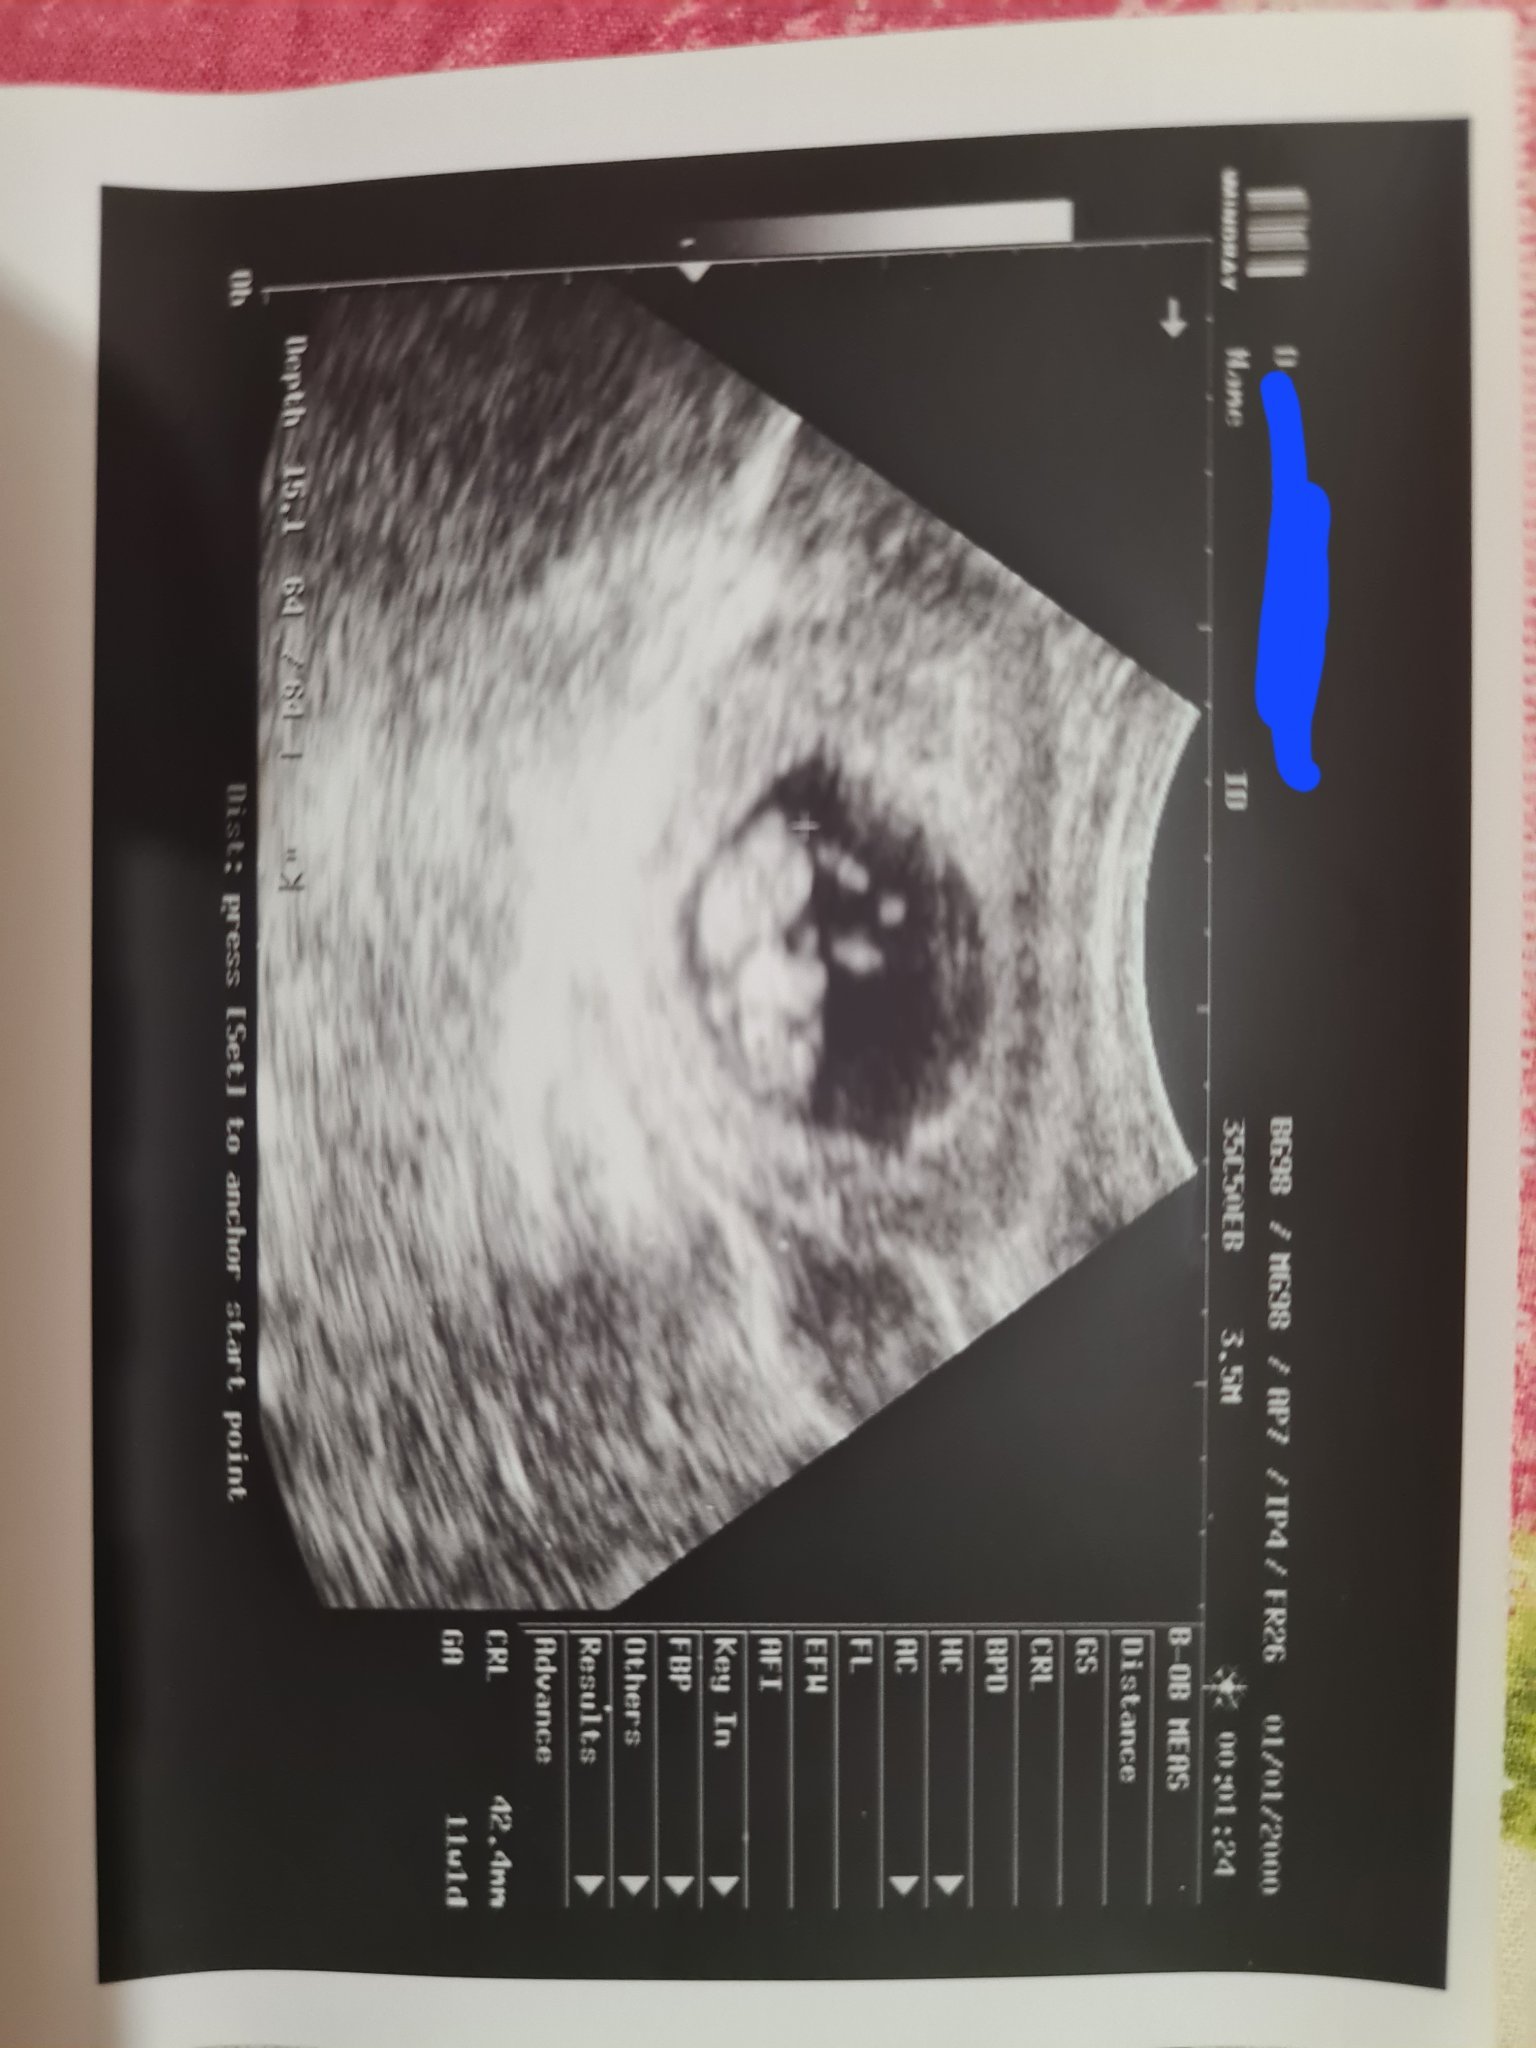

изписа ми вече витамини супле маман или нещо такова (още не съм го видяла в аптеката).. та да си дойда на думата- бебчето е пораснало много (сравнение с предния път беше само точка) и ще добавя снимка

колкото до симптоми, много ми се спи и ставам да пикая през 2часа. И последно, но не на последно място- официално съм с термин 07.01.2024г.